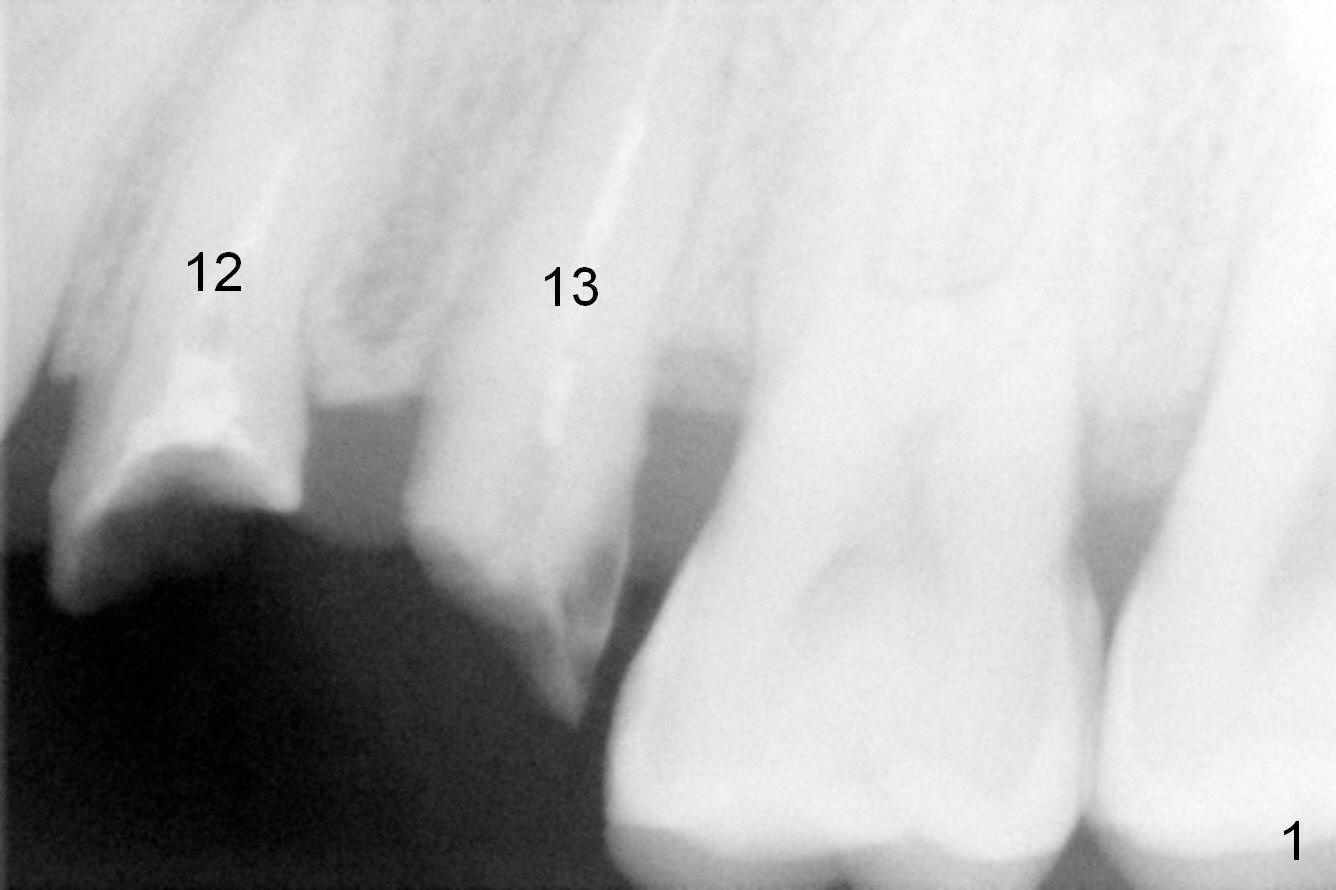

Taking 2 additional PAs with sensor 1 is frustrating (Fig.1,2), no apices shown.  Osteotomy is done smoothly with 2 mm pilot drill at 20 mm, 2.5 mm reamer at 17 mm, and 3 mm reamer at 14 mm and 4.5x20 mm tap at 17 mm.  The 1st intraop PA is taken with sensor 1 when 2 of 4.5x20 mm implants are placed (Fig.3); the implant at #12 is close to the root of the tooth #11.  The 2nd PA is taken with sensor 2: the apex of #11 touches the implant at #12 (Fig.4).  There is no separation when panoramic X-ray is taken (Fig.5).  Effort is exerted to re-direct the osteotomy twice (Fig.6: tap; Fig.7: implant) without success.  When the implant is removed, a PA is taken; it appears that the root of the tooth #11 has no damage (Fig.8).  To obtain the best recovery, socket preservation is carried out with 50/50 cortical/cancellous allograft mixed with Osteogen (Fig.12 *) and Collagen Dressing (Fig.9: #12).  A 2 (or 3)-unit provisional bridge (Fig.10: #12,13) is fabricated over the implant (Fig.9 I)/abutment (A) to cover these 2 sockets.  After acid etching #11 D surface (Fig.9 >) and relining (Fig.11 *), the provisional bridge is bonded to the tooth #11 (Fig.11,12 black >) so that bone graft will be less likely dislodged.